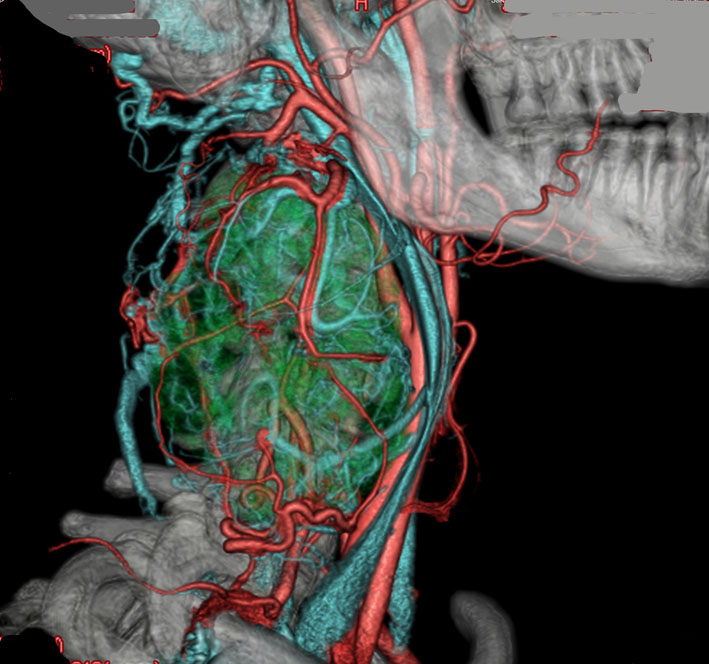

耳の聞こえと飲み込みが悪くなって発症(難聴と嚥下障害)した20代の患者さんのグロームス腫瘍 jugular paragangliomaです。左の頚動脈撮影 CAGでは,頸部の腫瘍におされて内頚動脈が前方に屈曲しています。外頚動脈から多くの血管が流入して血管腫のように濃い腫瘍陰影がみえます。右側の椎骨動脈撮影 VAGでは,頚静脈孔から頭蓋内の小脳延髄角部まで伸びた腫瘍が染まります。頭蓋内はPICAから頸静脈球と頸部には椎骨動脈の筋肉枝からの腫瘍血管がみられます。

頸部から頸静脈球を抜けてS上静脈洞内に入ります。これはクラスCかDか迷うところです。ちょっと難しい。またこのサイズでは,迷走神経と舌咽神経の機能を温存することができません。延髄方向へ伸展していますし年齢が若いので手術せざるを得ないものでした。